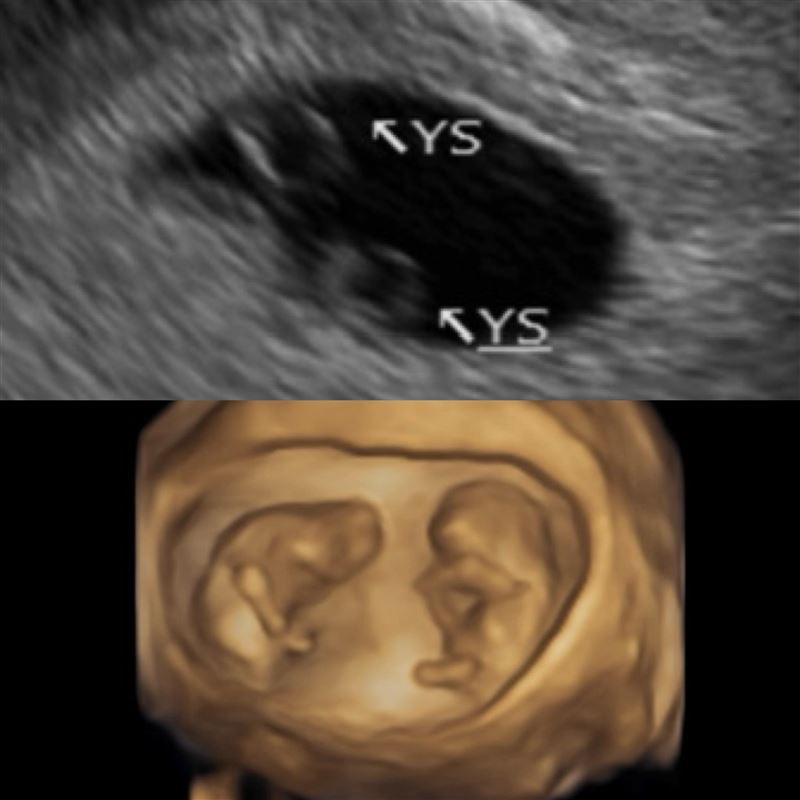

女星鄭家純(雞排妹)在2022年嫁給日籍老公Akira,婚後過得相當幸福,而先前發文才被猜測是否因為「害喜」才暈車的鄭家純,如今透過社群證實懷孕,且是同卵雙胞胎,引發一票粉絲留言恭喜。

鄭家純今(20日)透過臉書曬出寶寶超音波照片,透露已懷孕12週的震撼喜訊,由於鄭家純才在1月初經歷過流產噩耗,因此醫生曾建議要間隔3個月後再規劃自然懷孕,不過鄭家純不知道小產後排卵期會晚來報到,結果在錯誤時間點避孕,竟意外懷上小孩。